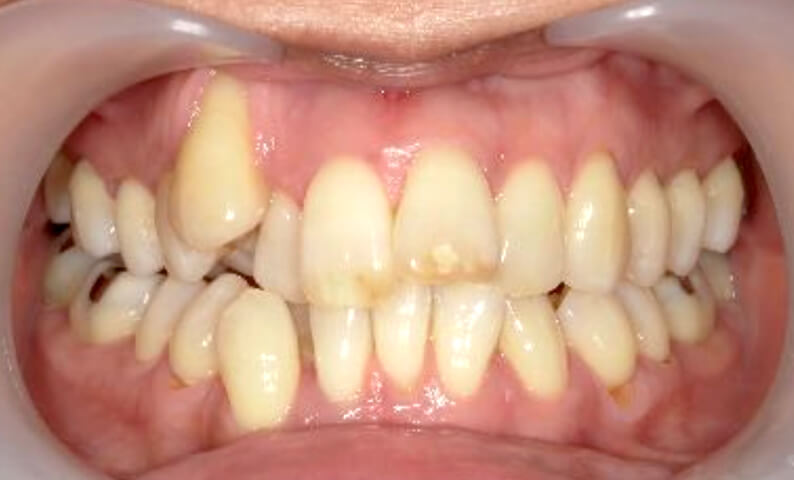

症例_002 下顎だけの部分矯正

治療期間:6ヶ月金額:21万円+税女性前歯のデコボコ下の前歯だけ

| Before | After |